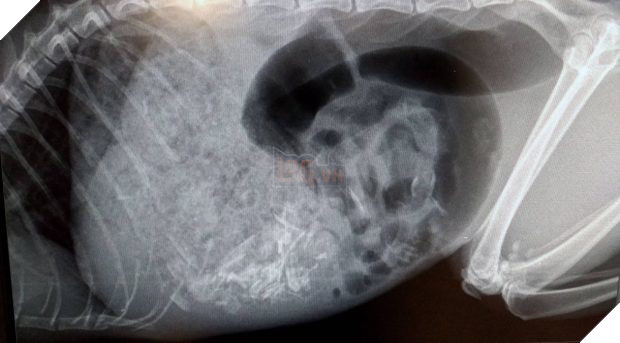

Bác sĩ Leanne Honess đã trực tiếp đứng ra để kiểm tra và điều trị cho chú mèo. Bước đầu chụp X quang, Leanne tìm thấy một con chip nhỏ được gắn trên thân của Rosie, đồng thời cũng phát hiện ra một sinh vật lạ vẫn còn khá nguyên vẹn đang nằm trọn trong dạ dày của chú mèo.

Từ hình ảnh chụp X quang cho thấy dạ dày của Rosie đã bị lấp đầy bởi một con chuột vẫn còn khá nguyên vẹn.

Trong lúc đó, bác sĩ Leanne cũng đã xác định được sinh vật lạ đang "chễm chệ" trong bụng của Rosie hóa ra là một con chuột với kích thước thước khá lớn. Do bản tính háu ăn nên mèo ta đã cứ thế mà nuốt chửng cả con chuột vào bụng, khiến dạ dày ứ đầy và bụng to phình một cách bất thường.